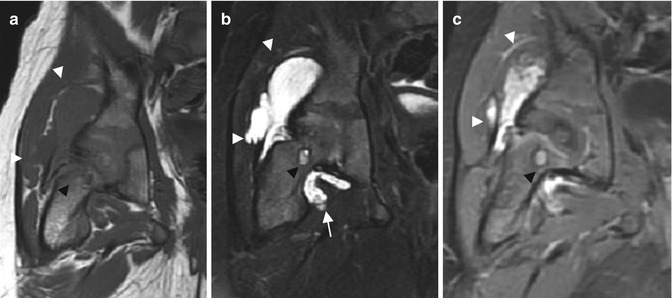

Synovial hemangioma of the hip. (a) Coronal T1-weighted MR image. (b) Coronal T2-weighted MR image with fat suppression. (c) Coronal T1-weighted MR image after Gadolinium contrast administration with fat suppression. Hemangioma demonstrates a low signal intensity on T1-WI, bright signal intensity on T2-WI and enhances after gadolinium administration (white arrowheads). Note the hypointense area under the femoral head related to hemosiderin deposition (arrow) and the erosive change of the anterior aspect of the femoral neck (black arrowhead)